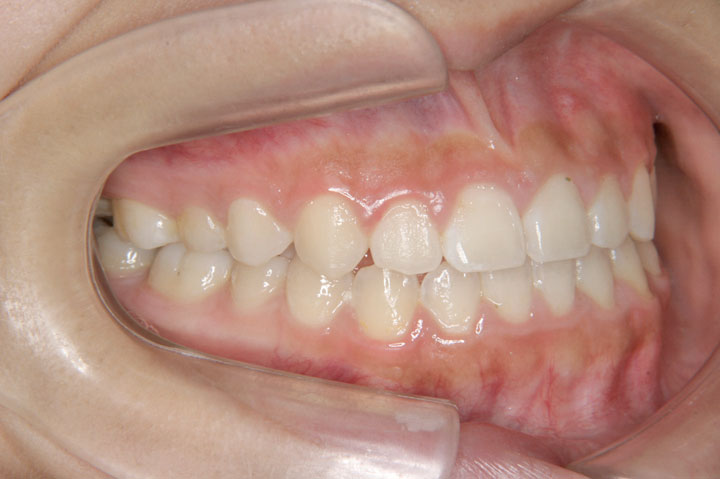

下顎の偏位と上顎右側小臼歯の萌出空隙が無いことを主訴に来院された小学校5年生の患者さんです。上顎第二大臼歯萌出前でしたので、リンガルアーチとセクショナルアーチを用いて第一大臼歯の遠心移動から開始しました。その後、非抜歯でデーモンブラケットを用いたエッジワイズ装置に移行しております。ほぼ一歯分の空隙不足でしたが、第二大臼歯萌出前に治療を開始できたことが非抜歯での矯正治療を行う上で、良かったと考えております。